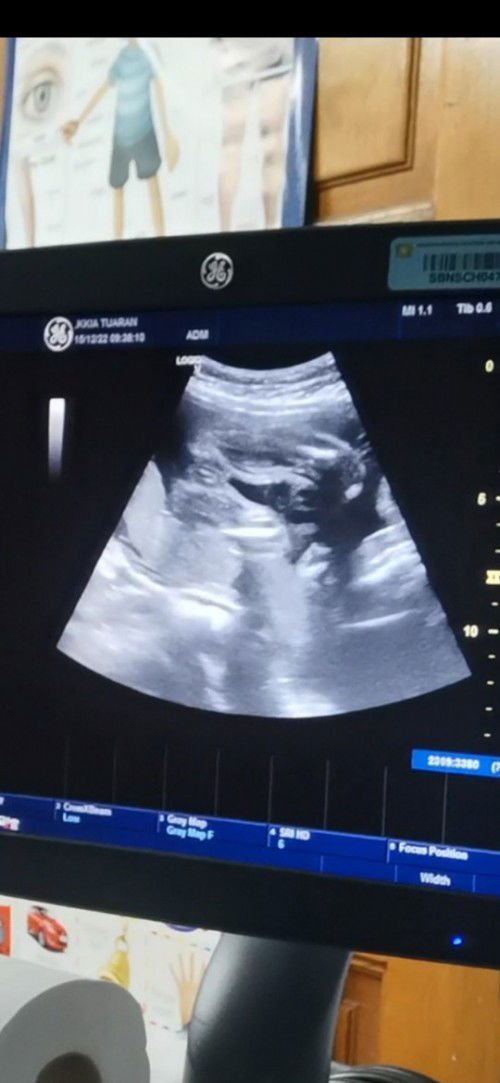

Nak tahu scan baby

Kalau cam nie baby girl atau boy ye